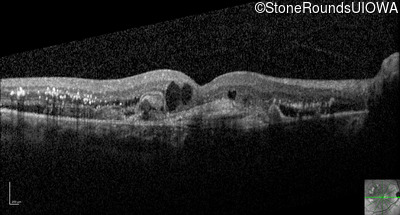

Optical Coherence Tomography - Right - 20/200 +1

Exemplar / OCT Stack

Infrared Fundus Photograph - Right - 20/200 +1

Exemplar